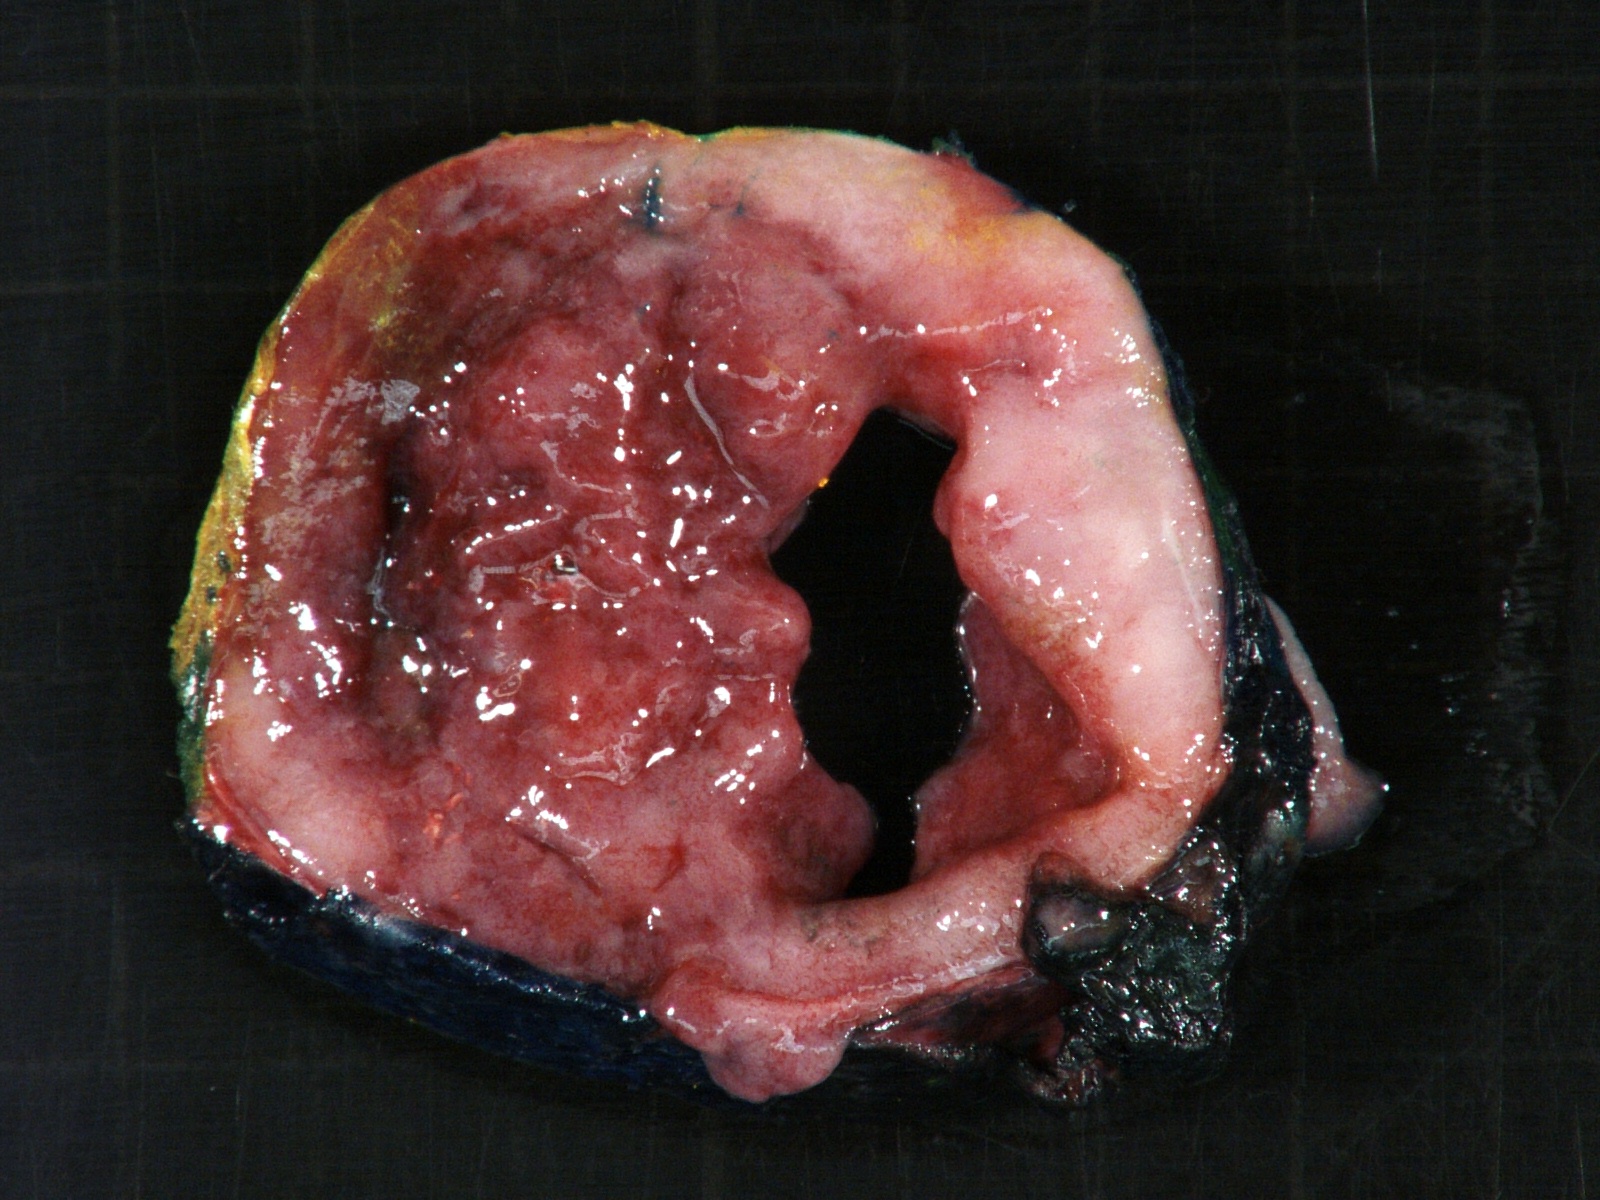

Gross description

- More homogeneous and mature appearance than neuroblastoma

- Varies by subtype, from circumscribed ovoid mass to large multilobulated tumor

- Stroma rich, nodular subtype: area(s) of stroma poor, immature tumor are usually hemorrhagic with well defined borders (J Natl Cancer Inst 1984;73:405)

- Calcification (chalky white, yellow areas) and cystic degeneration may occur

- If large, adrenal gland may be difficult to identify

Gross images